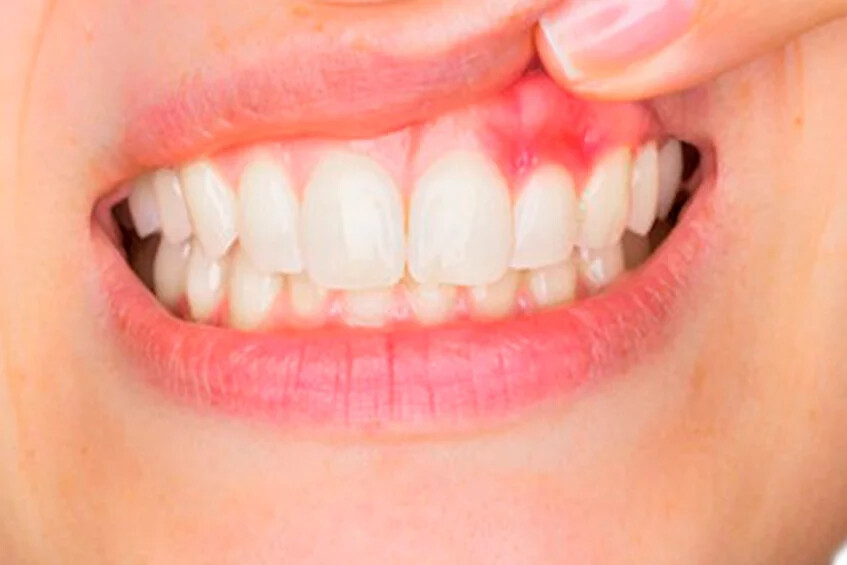

2. Swollen gums

While safe disease-free gums look solid and pink in color, gums that have gum disease can swell, turning red or purple in color.

5. Bleeding gums

Normally, healthy gums don’t bleed from daily tooth brushing or flossing; if your teeth bleed during your usual oral hygiene routine, you may have developed gum disease.